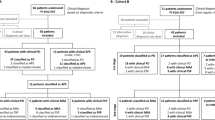

Training and validation

SVM and LR, combined with a PCA prior to classification (PCA-SVM and PCA-LR), were evaluated to classify ALS and PP patients and to generate ALS- and PP-specific metabolic brain patterns. In addition, SVM without prior feature transform was evaluated. For the SVM implementation, a L1 soft margin SVM with linear kernel was considered (MATLAB version 2016b, The MathWorks Inc., Massachusetts, USA). As illustrated in Fig. 1, all binary classifiers were trained and tested by applying tenfold cross-validation (CV) while preserving the balance in size of both classification groups. Within each tenfold, an inner loop tenfold CV was defined over the training folds to tune classifier-specific parameters. For SVM, the soft margin and kernel scale hyperparameters were optimized by applying a grid search over the nested inner loop while for LR, the parameters controlling the elastic-net and overall regularization were determined by cyclical coordinate descent using the Glmnet package [28]. The tenfold CV scheme was iterated ten times randomly, and therefore, performance results were interpreted as average values together with the corresponding standard deviation. Classification performance was assessed by the receiver operating characteristic (ROC) curves with corresponding area under the curve (AUC) values, and by the sensitivity and specificity (true positives are the patients having ALS diagnosed by the model as ALS). Moreover, Pearson correlations were determined between the individual pattern expression scores (averaged over the ten random iterations) as determined by PCA-SVM, PCA-LR, and SVM to compare the output of three classifiers for direct classification between ALS and PP. Besides direct classification between ALS and PP, ALS- and PP-specific brain patterns were generated by classifying HC versus ALS and PP respectively using either PCA-SVM, PCA-LR, or SVM. By applying tenfold CV over ten random validation schemes, a series of ten pairs of pattern expression scores for both the ALS- and PP-specific brain pattern was obtained for each subject. To evaluate a classification based on these ALS- and PP-specific pattern expression scores, a linear SVM was trained and evaluated by tenfold CV and ROC curves with corresponding AUC, sensitivity, and specificity were determined to allow comparison with direct classification between ALS and PP. Additionally, the RV coefficient, which is a multivariate generalization of the squared Pearson correlation coefficient with values in the interval [0, 1] [29], was determined for the pairs of individual ALS- and PP-specific pattern expression scores (averaged over the ten random iterations) as determined by the three classifiers to compare the output of PCA-SVM, PCA-LR, and SVM in terms of disease-specific pattern expression scores.